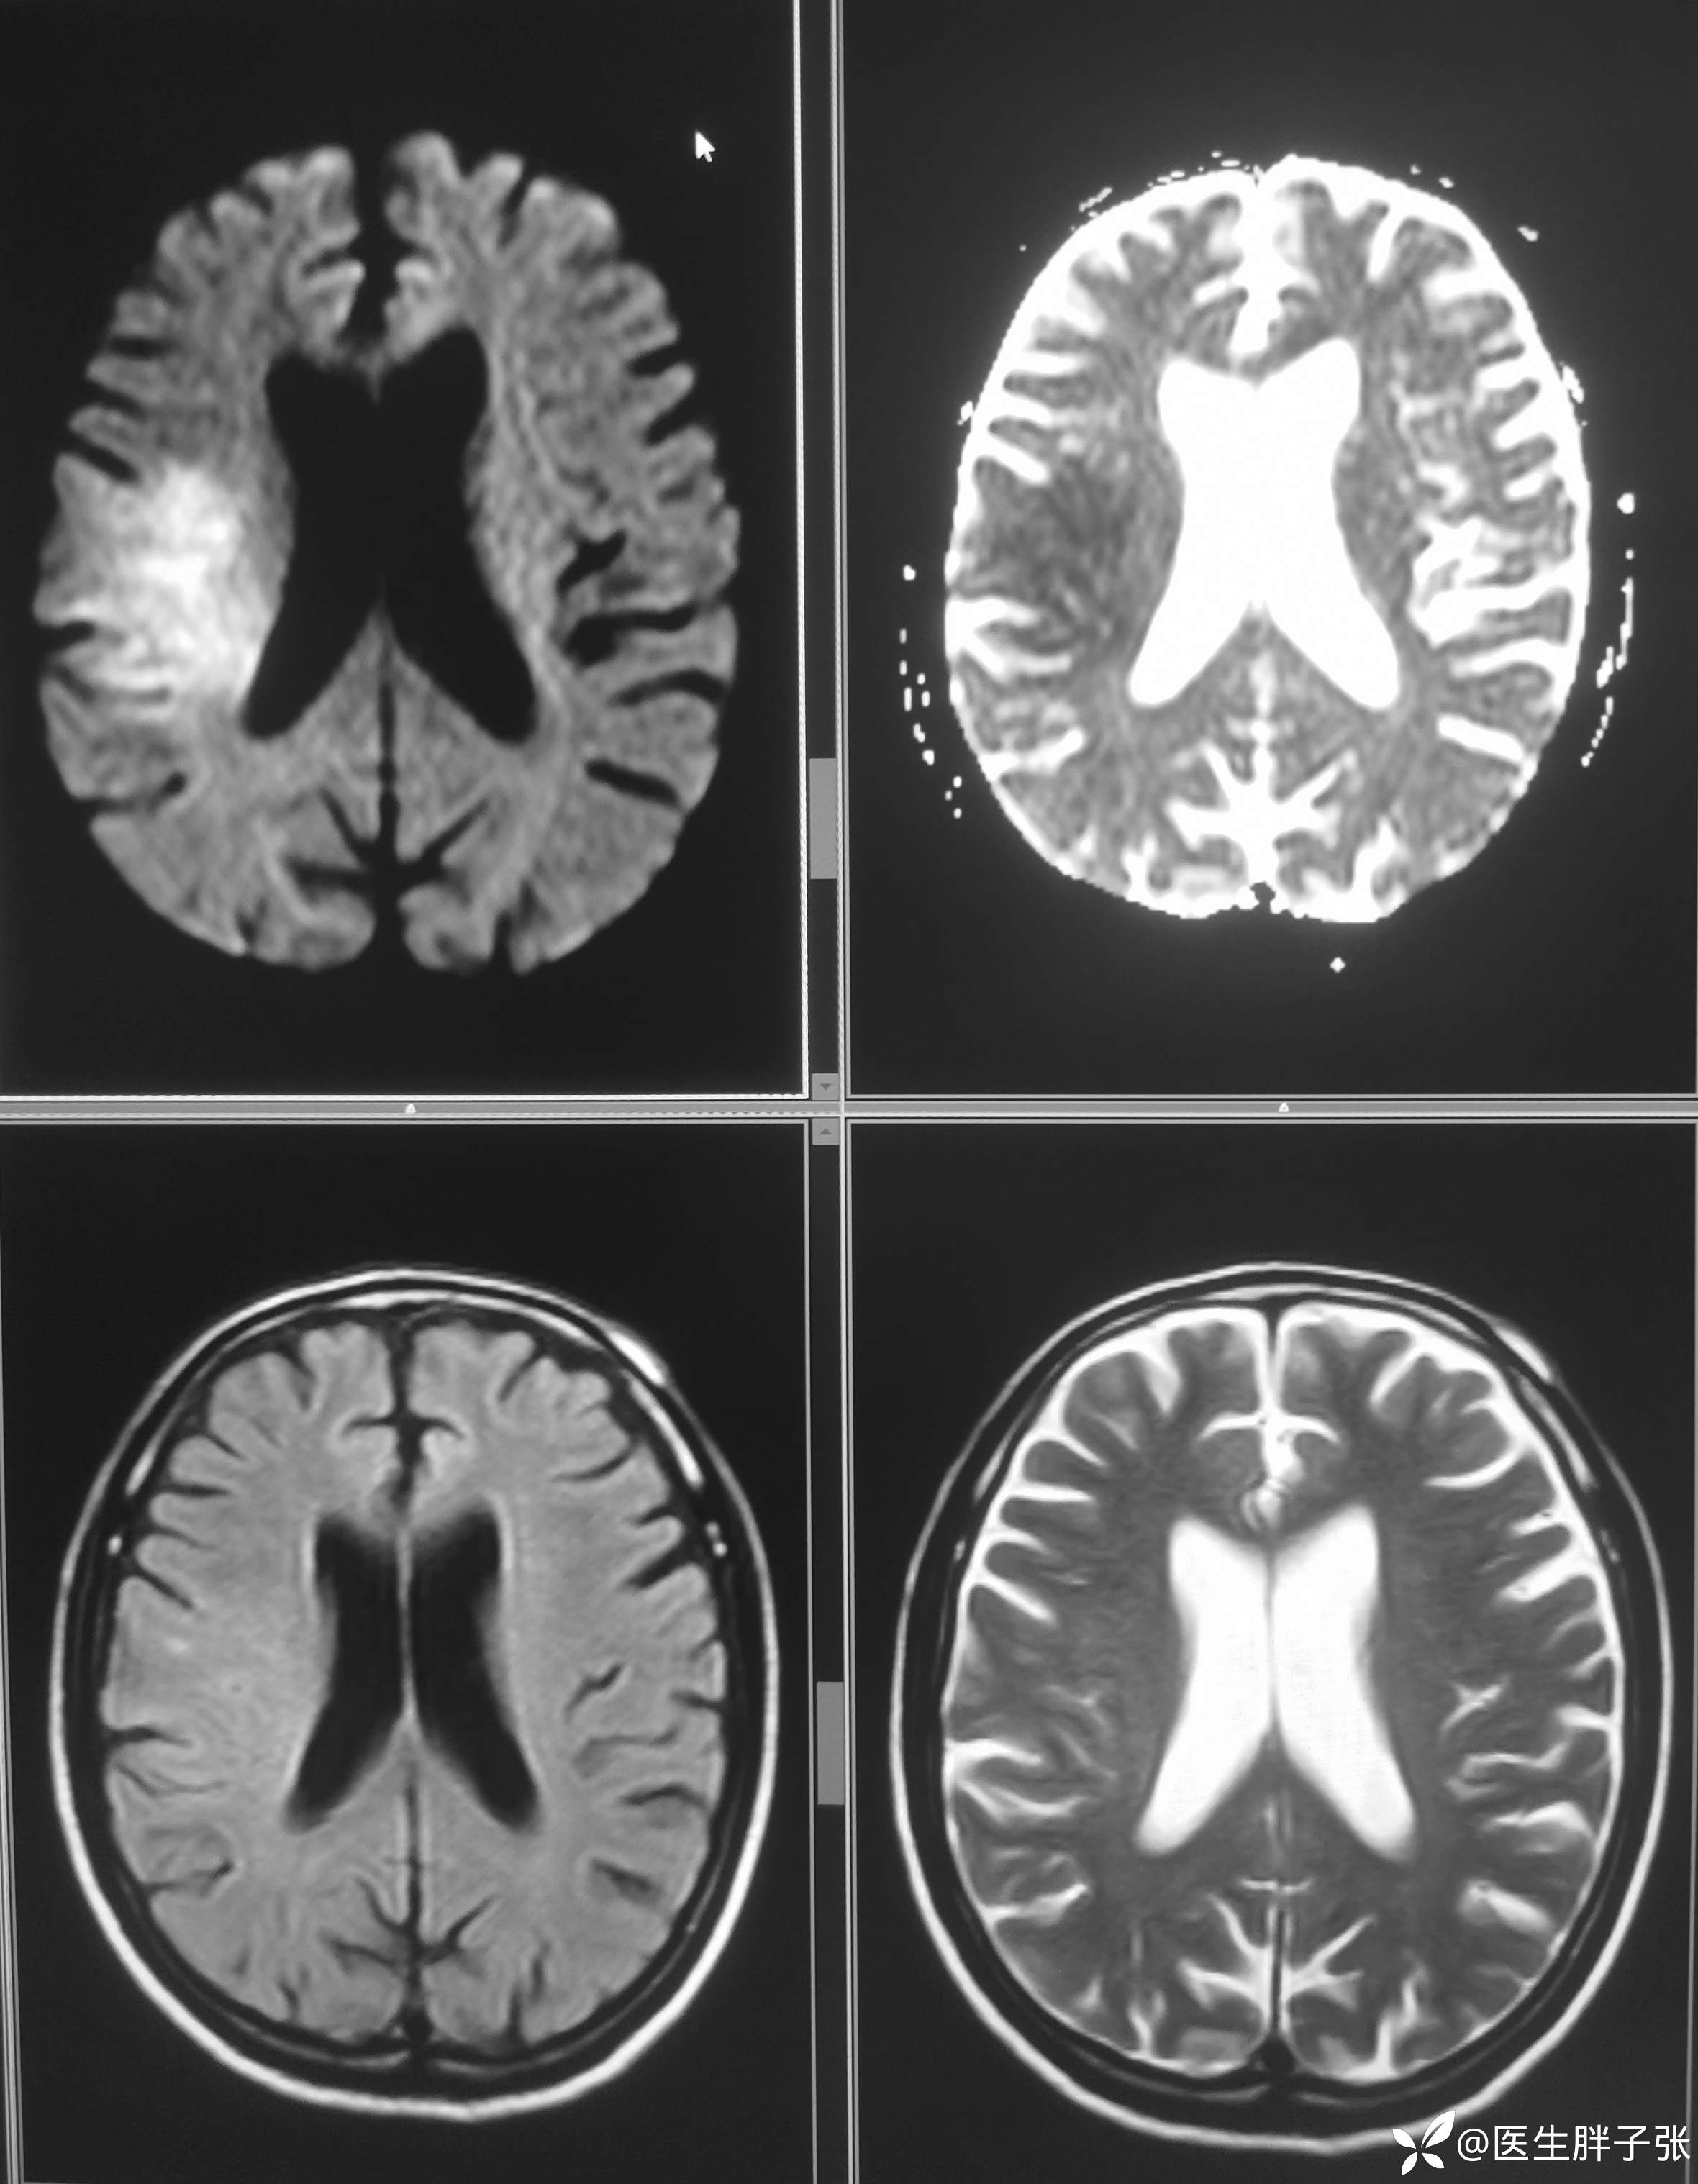

颅脑MR:右侧颞叶新近梗死灶;老年性脑改变;右侧大脑中动脉部分M2段及以远未见显示,建议头颈部CTA检查。

患者为醒后卒中患者,幸运的是恰好晨起交班的时候来院,恰好能查核磁,核磁提示存在DWI-FLAIR错配